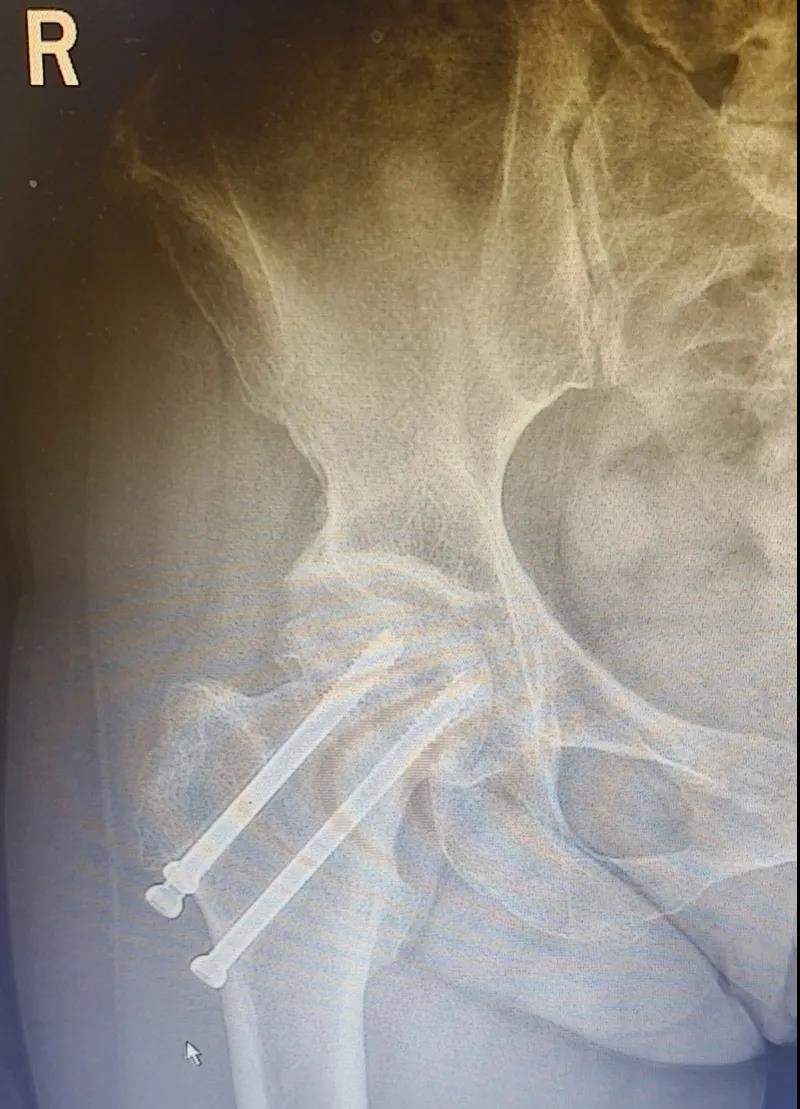

據(jù)李女士自述,自己于3年前因外傷致右股骨頸骨折,當(dāng)時在其他醫(yī)院做了右股骨頸骨折閉合復(fù)位螺釘內(nèi)固定術(shù),一年后右髖出現(xiàn)疼痛并逐漸加重,且休息不能緩解,行走時就像有座山壓身上一樣。

結(jié)合病癥表現(xiàn)及影像顯示,李女士被診斷為“右股骨頸骨折術(shù)后股骨頭壞死”,需要盡快做手術(shù)。

(△術(shù)前影像,右股骨頸骨折內(nèi)固定術(shù)后股骨頭壞死)